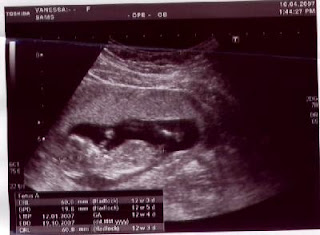

Já não postava faz tempo, mas a verdade é que o tempo passa e nem damos por ele. Já completei os três meses e pela ecografia de ontem vamos ter uma Inês daqui a uns meses. Mexe-se muito para os papás verem e esteve sempre de cabeça para baixo... Espero poder postar mais frequentemente daqui para a frente.

Em cima, fica a imagem da ecografia da Inesocas.